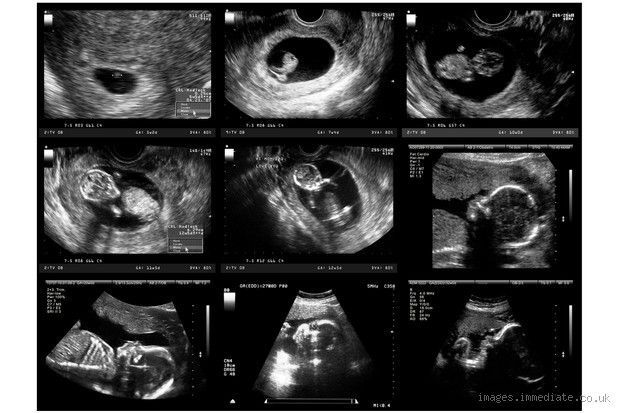

Can Ultrasound Be Wrong in Early Pregnancy? What You Need to Know

How Accurate Is Ultrasound in Early Pregnancy?

Okay, here’s the thing: ultrasound is usually pretty accurate, but it’s not infallible, especially in the early weeks. If you’re just six weeks pregnant and go in for your first ultrasound, it’s possible that your baby might not be visible yet or that a heartbeat may not be detectable. I know that can be nerve-wracking, especially if you're hoping for good news. The thing is, at this stage, everything is still developing rapidly, so things can be a little blurry.

One of the most common reasons for early ultrasound inaccuracies is timing. Early pregnancy can be tricky to measure, especially if you’re unsure of when your last period was or if your cycle is irregular. Even a few days can make a big difference in what you see on the screen.

Machine Sensitivity and Technician Experience

Misinterpretation of Results

Honestly, this one really freaks me out. Sometimes, even if the equipment and timing are perfect, the results can be misinterpreted. Ultrasounds show a lot of data, and there’s a lot of room for human error in analyzing it. For instance, in early pregnancy, the gestational sac or the yolk sac might be visible, but the embryo itself might not be clear enough to be seen. It doesn’t mean there’s an issue, but it can certainly lead to some confusion.